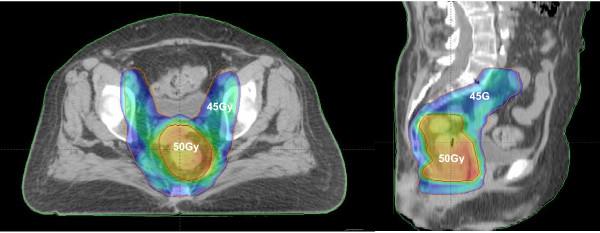

This retrospective analysis reports on the comparative outcome of acute gastrointestinal (GI) and genitourinary (GU) toxicities between conformal radiation therapy (CRT) and intensity modulated radiation therapy (IMRT) techniques in the treatment of patients with pelvic tumors.

From January 2002 to December 2008, 69 patients with pelvic tumors underwent whole pelvic CRT and 65 underwent whole pelvic IMRT to treat pelvic lymph nodes and primary tumor regions. Total dose to the whole pelvis ranged from 50 to 50.4 Gy in 25 to 28 daily fractions. Chemotherapy (CT) regimen, when employed, was based upon primary tumor. Acute GI and GU toxicities were graded by RTOG/EORTC acute radiation morbidity criteria.

方法

2002 年 1 月至 2008 年 12 月,69 例盆腔肿瘤患者接受全盆腔 CRT,65 例接受全盆腔 IMRT,以治疗盆腔淋巴结和原发肿瘤区域。全盆腔总剂量为 50 至 50.4Gy,分 25 至 28 次每日分割。化疗(CT)方案根据原发肿瘤而定。急性 GI 和 GU 毒性采用 RTOG/EORTC 急性放射损伤标准分级。